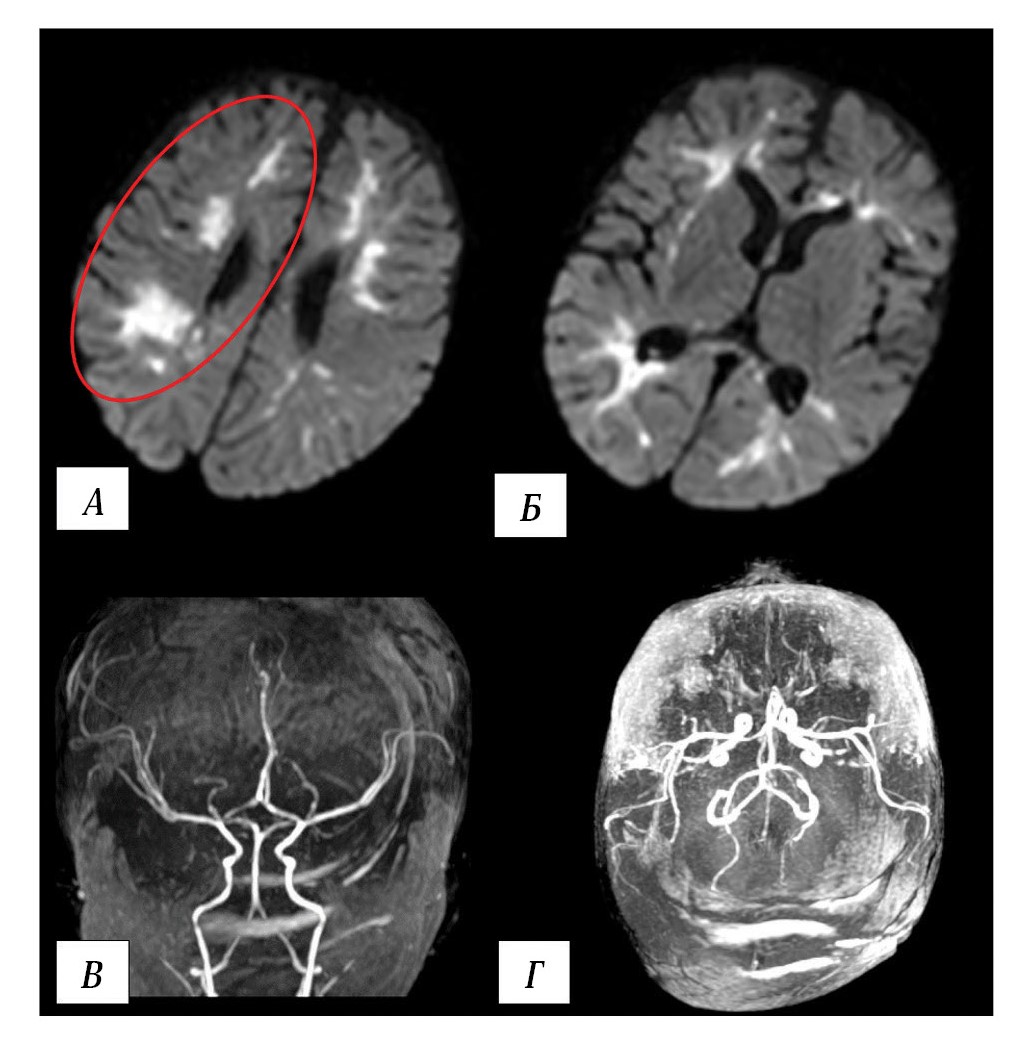

Brain MRI revealed watershed infarctions in both hemispheres (Fig. 5).

Fig. 5. Results of patient B. MRI on day 2 postoperatively.

A, B — brain MRI. DWI, axial plane. Watershed infarctions in both cerebral hemispheres. Red oval outlines the most extensive area in the right hemisphere; similar regions are observed in the left hemisphere. C, D — MR angiography, 3D reconstruction. Intracranial arterial blood flow remains intact.